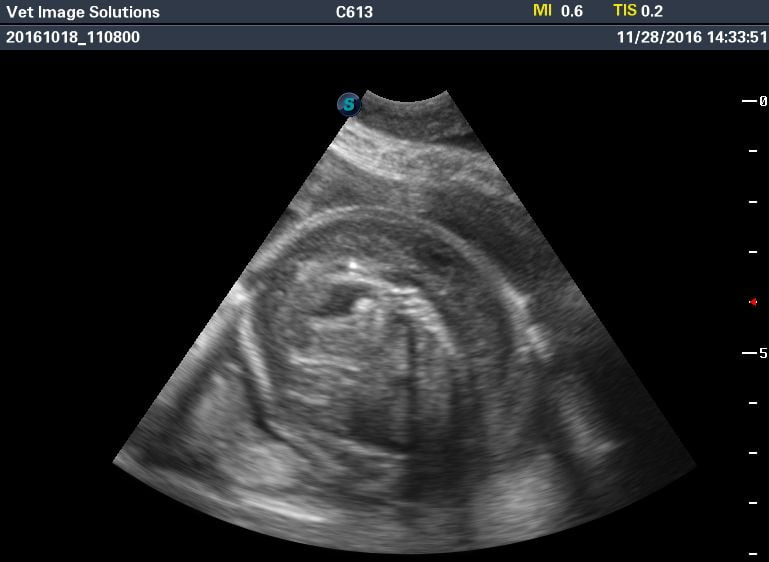

This is a late canine pregnancy scan, on a bulldog in Croydon (due within the next 7 days). Acoustic shadows are now being cast from the solidified bone of the puppies’ rib cages, and the four chambers of the foetal hearts can be clearly seen.